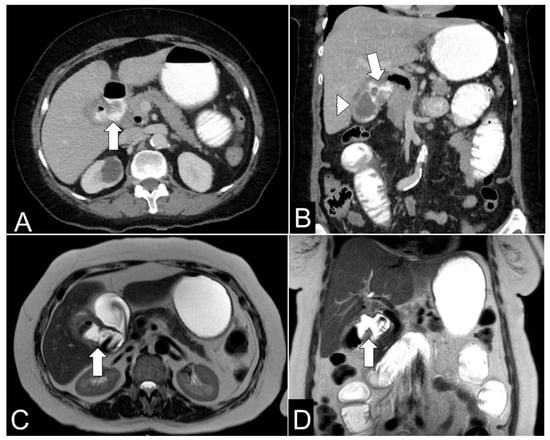

Persistent Vomiting and Epigastric Pain in an Adolescent: A Case of Superior Mesenteric Artery Syndrome Unmasked

Background and Clinical Significance: Superior mesenteric artery syndrome (SMAS) is a rare and often underdiagnosed cause of proximal intestinal obstruction, resulting from compression of the third portion of the duodenum between the SMA and the aorta. It typically occurs in individuals with significant [...] Read more.

Background and Clinical Significance: Superior mesenteric artery syndrome (SMAS) is a rare and often underdiagnosed cause of proximal intestinal obstruction, resulting from compression of the third portion of the duodenum between the SMA and the aorta. It typically occurs in individuals with significant weight loss due to mesenteric fat depletion. CasePresentation: We report the case of a 14.5-year-old female presented with a 6-day history of intractable vomiting and epigastric pain, on a background of intermittent vomiting over the preceding six months associated with a 7 kg unintentional weight loss, culminating in inability to tolerate oral intake. Her clinical course was complicated by a transient episode of blurred vision, numbness, and incoherent speech, initially suspected to be a neurological event. Extensive gastrointestinal and neurological investigations were inconclusive. Elevated fecal calprotectin levels raised suspicion for inflammatory bowel disease, given her family history, though endoscopy and histopathology were unremarkable. Advanced imaging ultimately demonstrated a markedly reduced aortomesenteric angle (6°) and distance (4 mm), confirming the diagnosis of SMAS. The patient was initially managed conservatively with total parenteral nutrition (TPN), achieving partial weight gain of 5 kg after 8 weeks of TPN. Due to persistent duodenal compression, surgical intervention was required. At 7-month follow-up, the patient remained symptom-free with restored nutritional status and a good weight gain. Conclusions: This case highlights the importance of considering SMAS in adolescents with chronic upper gastrointestinal symptoms and significant weight loss. Early recognition and appropriate imaging are essential to diagnosis, and timely surgical management can lead to excellent outcomes when conservative treatment is insufficient. Full article